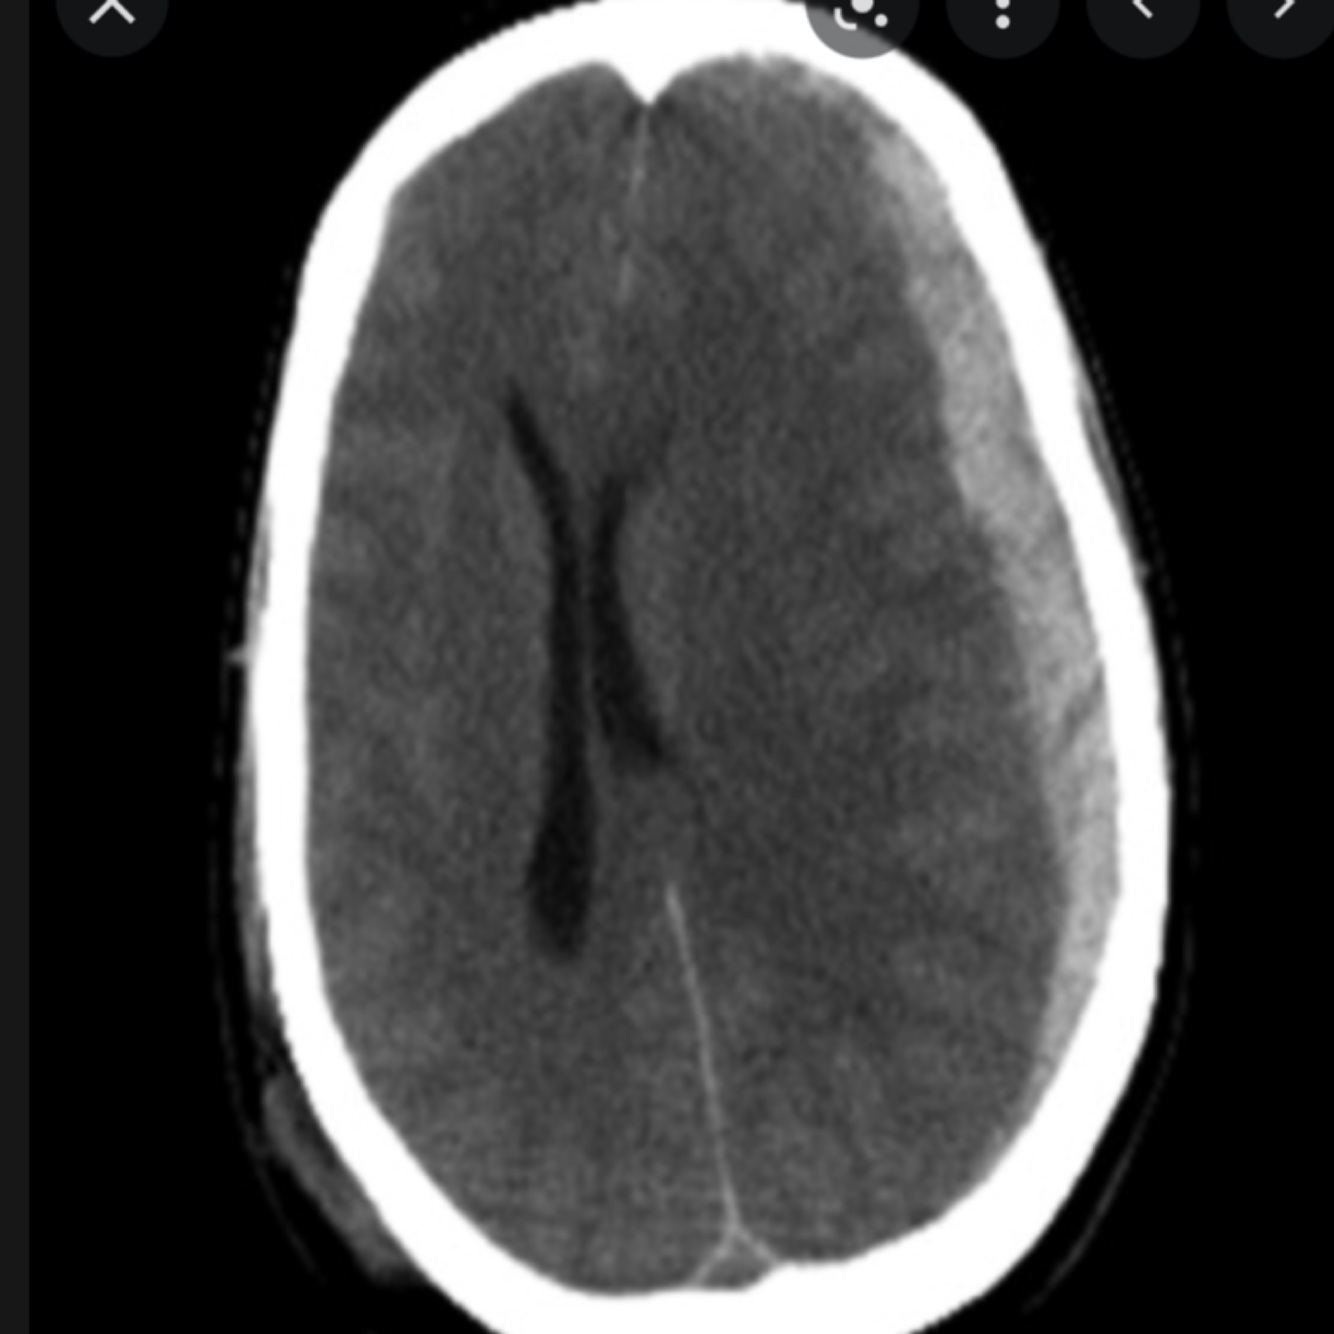

Subdural haemorrhage

This is a hemorrhage between the dura mater and arachnoid mater.

They may be acute, subacute, and chronic, but tend to present more gradually than extradural hemorrhages, with gradually increasingheadache and confusion.

They tend to occur in older patients.

Other risk factors include historic head trauma, alcoholism, and anticoagulation.

On CT, a crescent-shaped hematoma is diagnostic. This occurs as expansion of the haemorrhage is not limited by skull sutures, so follows the contour of the skull.

Neurosurgical intervention may be needed, if the haemorrhage is severe and symptomatic enough.

Acute subdural haemorrhage

Haemorrhage flows contour of skull as not limited by skull sutures

Subdural haemorrhage is caused by rupture of the bridging veins in the outermost meningeal layer. They occur between the dura mater and arachnoid mater. On a CT scan they have a crescent shape and are not limited by the cranial sutures (they can cross over the sutures).

On CT imaging they similarly are crescentic in shape, not restricted by suture lines and compress the brain (‘mass effect’). In contrast to acute subdurals (hyperdense (bright)), chronic subdurals are hypodense (dark) compared to the substance of the brain.